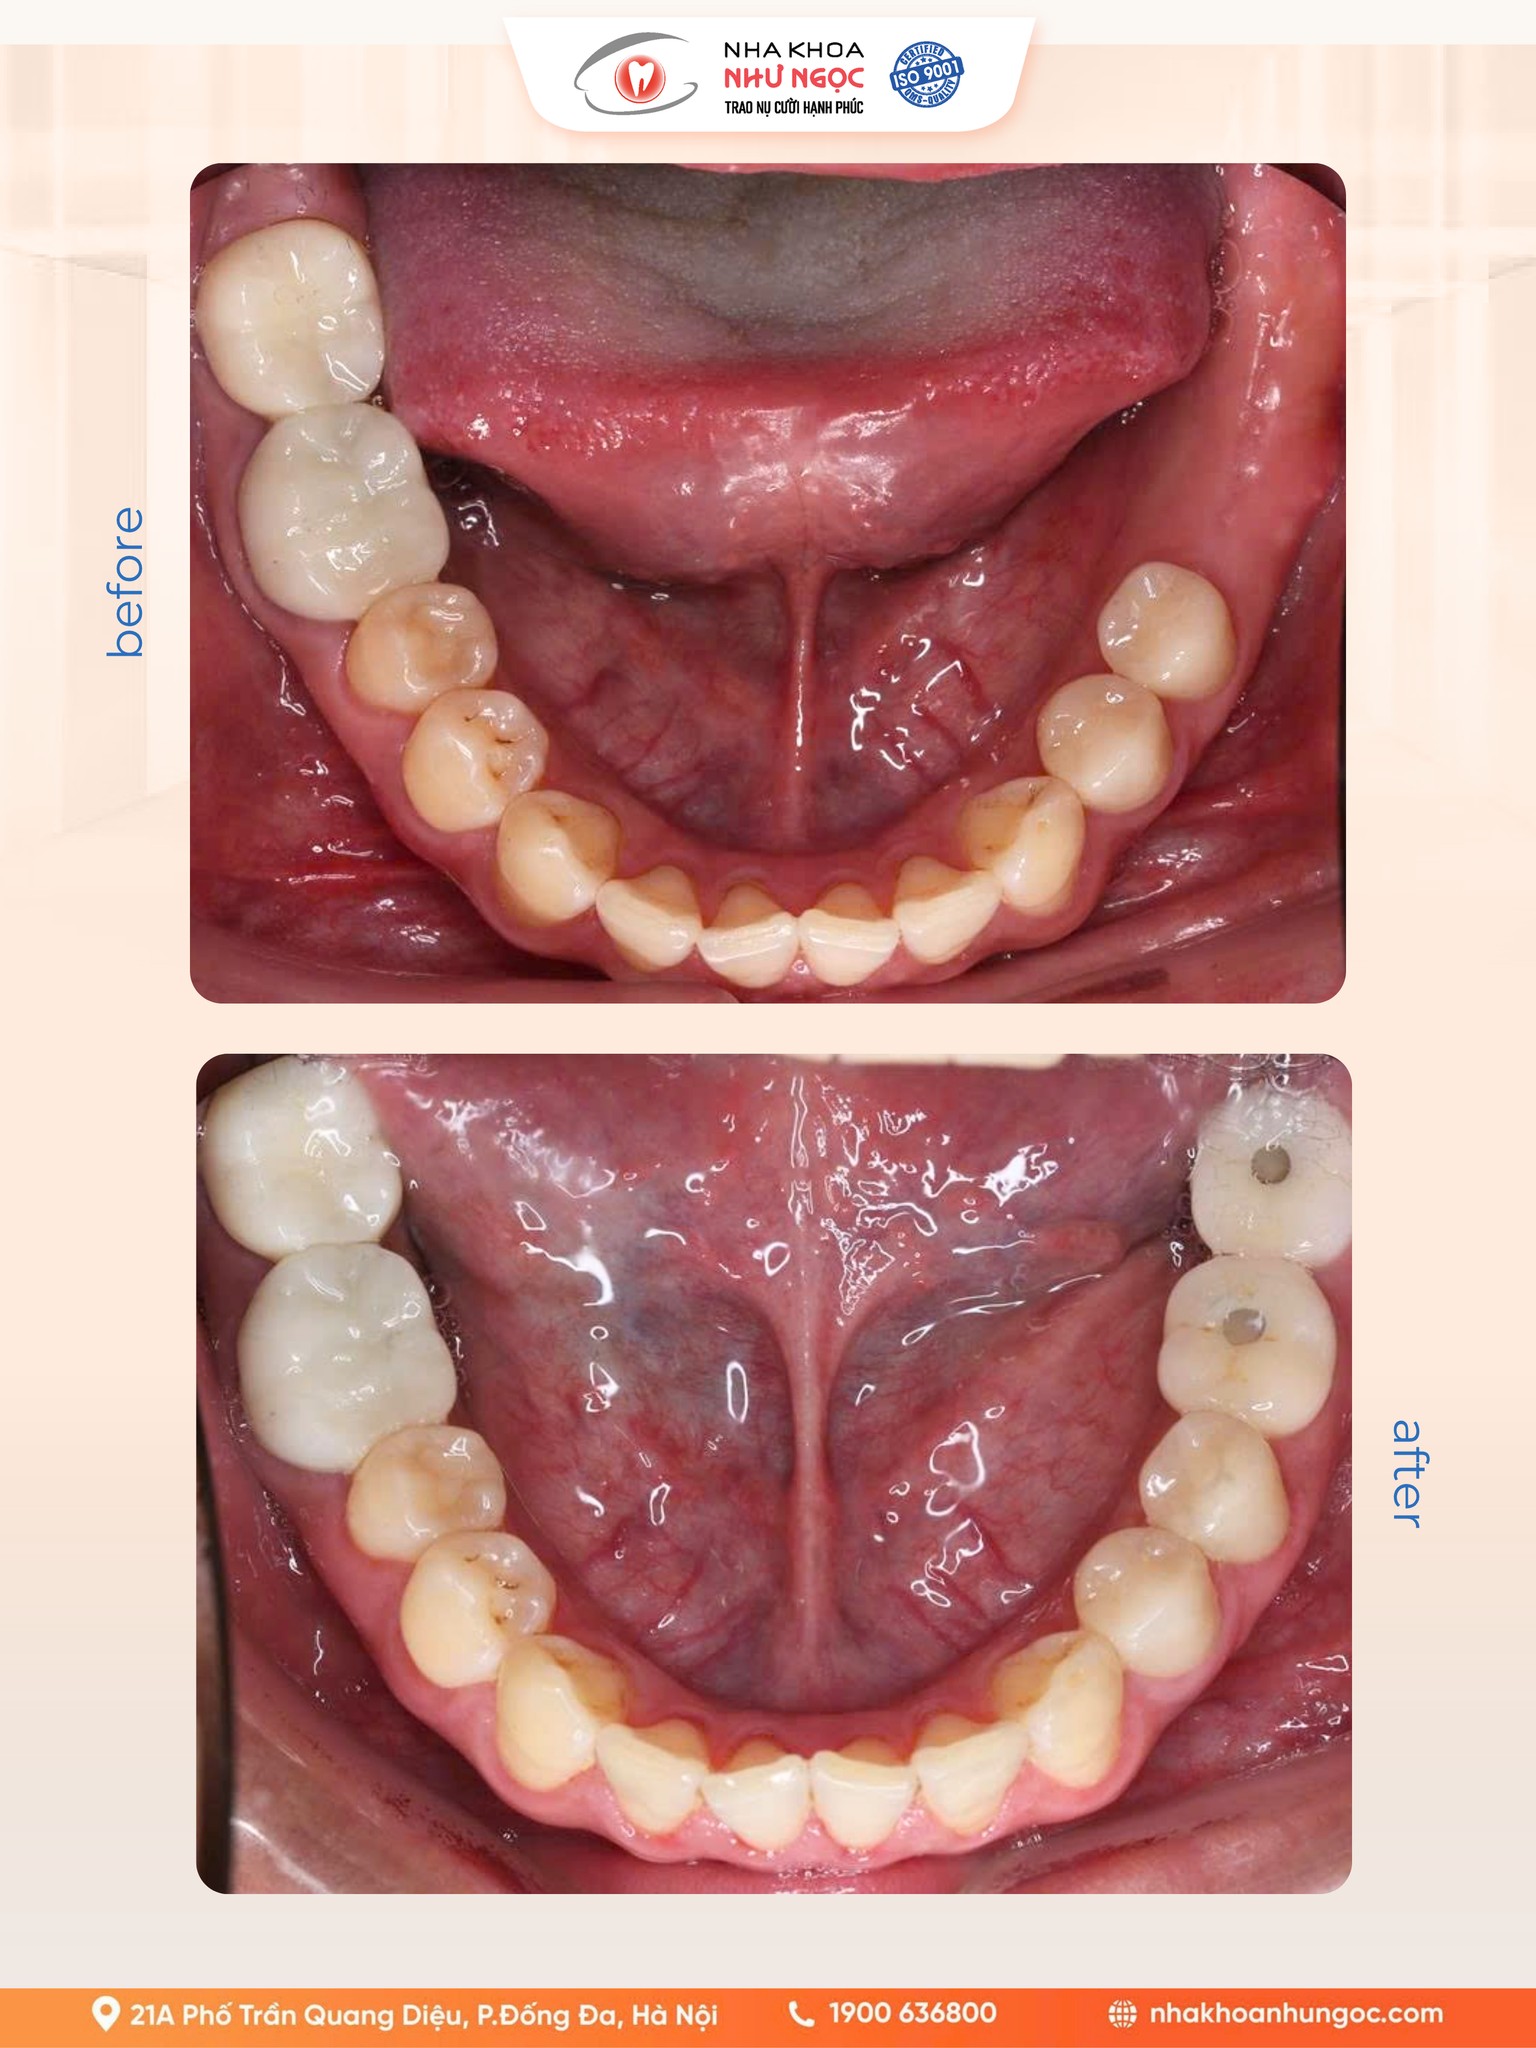

Trong nha khoa hiện đại, độ chính xác là chìa khóa quyết định thành công của một ca cấy ghép Implant. Và tại Nha khoa Như Ngọc, chúng tôi ứng dụng những công nghệ tiên tiến nhất để đảm bảo...